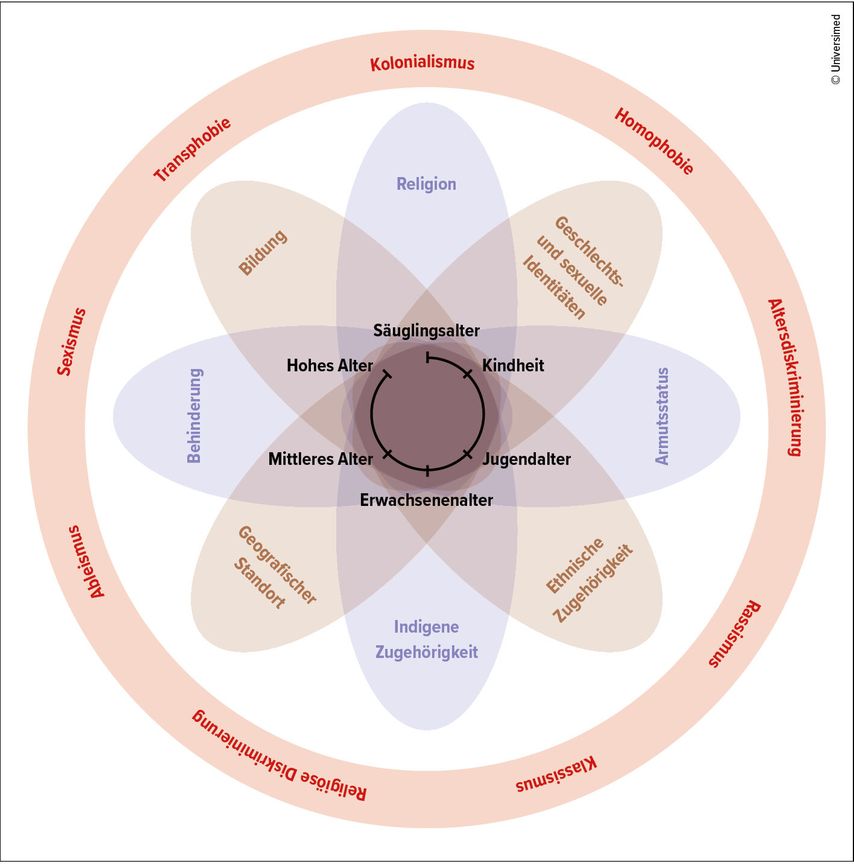

Der Begriff Intersektionalität stammt aus der Genderforschung und wurde 1989 von der US-amerikanischen Juristin und Bürgerrechtsaktivistin Kimberlé Crenshaw geprägt.Der Begriff verweist auf die Metapher der Straßenkreuzung (engl.: „intersection“): So wie ein Mensch im Straßenverkehr aus mehreren Richtungen gleichzeitig von anderen Fahrzeugen getroffen werden kann, können auch Rassismus, Sexismus, Klassismus, Sprachbarrieren undandere Diskriminierungsformen gleichzeitig zutreffen und eine eigene Form der Benachteiligung erzeugen, die durch die Betrachtung nur einer Achse unsichtbar bleibt (Abb.1). Anschaulich zeigt das der Fall „DeGraffenreid v. General Motors“ (1976): Arbeiterinnen of Color klagten, weil sie bei Einstellungen und Entlassungen benachteiligt wurden. GM wies darauf hin, dass das Unternehmen Männer of Color (in der Produktion) und „weiße“ Frauen (in Bürobereichen) beschäftige, also weder „rassistisch“ noch „sexistisch“ sei. Das Gericht verlangte eine getrennte Prüfung von Rasse oder Geschlecht und lehnte die Klage ab – genau dadurch blieb die spezifische Benachteiligung von Frauen of Color an der Schnittstelle beider Kategorien unberücksichtigt.

Abb. 1: Das Intersektionalitätsrad („The Intersectionality Wheel“; modifiziert nach Intersectionality resource guide and toolkit 2022)2

Übertragen auf die aktuelle Gesundheitsversorgung heißt das: Eine Frau mit COPD, Migrationsgeschichte, geringem Einkommen undeingeschränkten Deutschkenntnissen begegnet in jeder Versorgungsetappe anderen Hürden als ein gleichaltriger „autochthoner“ österreichischer Mann – selbst bei identischer Lungenfunktion. Intersektionalität macht diese überkreuzten Belastungen sichtbar und liefert damit einen praktischen Rahmen, Angebote, Kommunikation und Zugänge passgenau zu gestalten. Ein Verständnis von Intersektionalität kann damit zu einem hilfreichen Ansatz werden. Sie hilft, Kommunikationswege, Terminorganisation, Reha-Zugänge und Nachsorge patient:innen-orientiert zu gestalten. Handbücher wie der „Intersectionality Resource Guide“2 und einschlägige Quellen – etwa der Charité Berlin3 – geben hierfür Beispiele für Fortbildung und Orientierung.